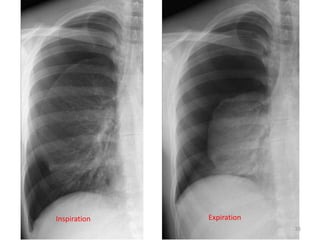

Inspiration Expiration